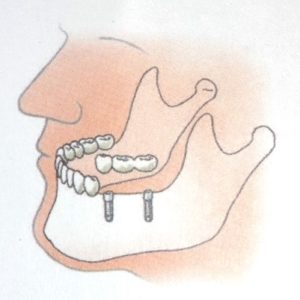

- Bij het ontbreken van alle tanden en kiezen.

- worden twee of meer implantaten geplaatst. Daarop worden knopjes of staafjes gemaakt waarop een overkappingsprothese vastklikt. Deze is uitneembaar, maar zit wel veel vaster dan een normale gebitsprothese. Soms wordt er een niet-uitneembare brug op vervaardigd, maar dan heb je wel tenminste vier implantaten nodig en is de behandeling veel duurder omdat de verzekeraar een dergelijke behandeling in het algemeen niet vergoedt.